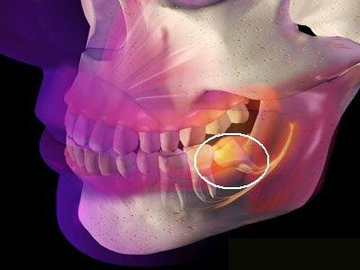

智齒是口腔中的第三大臼齒,有時候由于各種原因需要拔除,拔智齒是一項復(fù)雜的手術(shù),需要專業(yè)的牙醫(yī)進(jìn)行操作,許多人在考慮拔智齒時,最關(guān)心的問題之一就是拔智齒要花多少錢,本文將詳細(xì)解析拔智齒的費用及相關(guān)因素。

1、智齒位置:智齒的位置是影響拔除費用的重要因素之一,智齒的位置越深,手術(shù)難度越大,拔除費用也就越高。

2、手術(shù)復(fù)雜性:拔智齒手術(shù)的復(fù)雜性也會影響費用,如果智齒生長位置正常,手術(shù)相對簡單;如果智齒被埋在骨頭里,需要切開牙齦和骨頭,手術(shù)難度增大,費用相應(yīng)增加。

1、術(shù)前檢查:拔智齒前需要進(jìn)行口腔檢查、X光片等檢查,以了解智齒的位置和周圍結(jié)構(gòu),這些檢查費用也是拔智齒總費用的一部分。